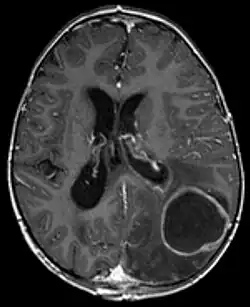

_--_showing_a_small_ring-enhancing_lesion_with_mild_surrounding_edema_adjacent_to_the_ventricular_catheter_and_ventricular_dilatation..jpg)

Zunächst ist eine bildgebende Untersuchung erforderlich, die zumeist mittels kontrastmittelgestützter Computertomographie oder Magnetresonanztomographie erfolgt. Hier sind in den meisten Fällen der entzündliche Herd, das umgebende Ödem sowie eine Anreicherung des Kontrastmittels zu erkennen.